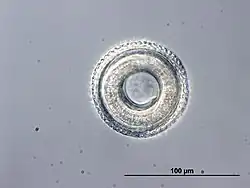

Toxocara est un genre de nématodes (les nématodes sont un embranchement de vers non segmentés, recouverts d'une épaisse cuticule et menant une vie libre ou parasitaire) et de la famille des Toxocaridae.